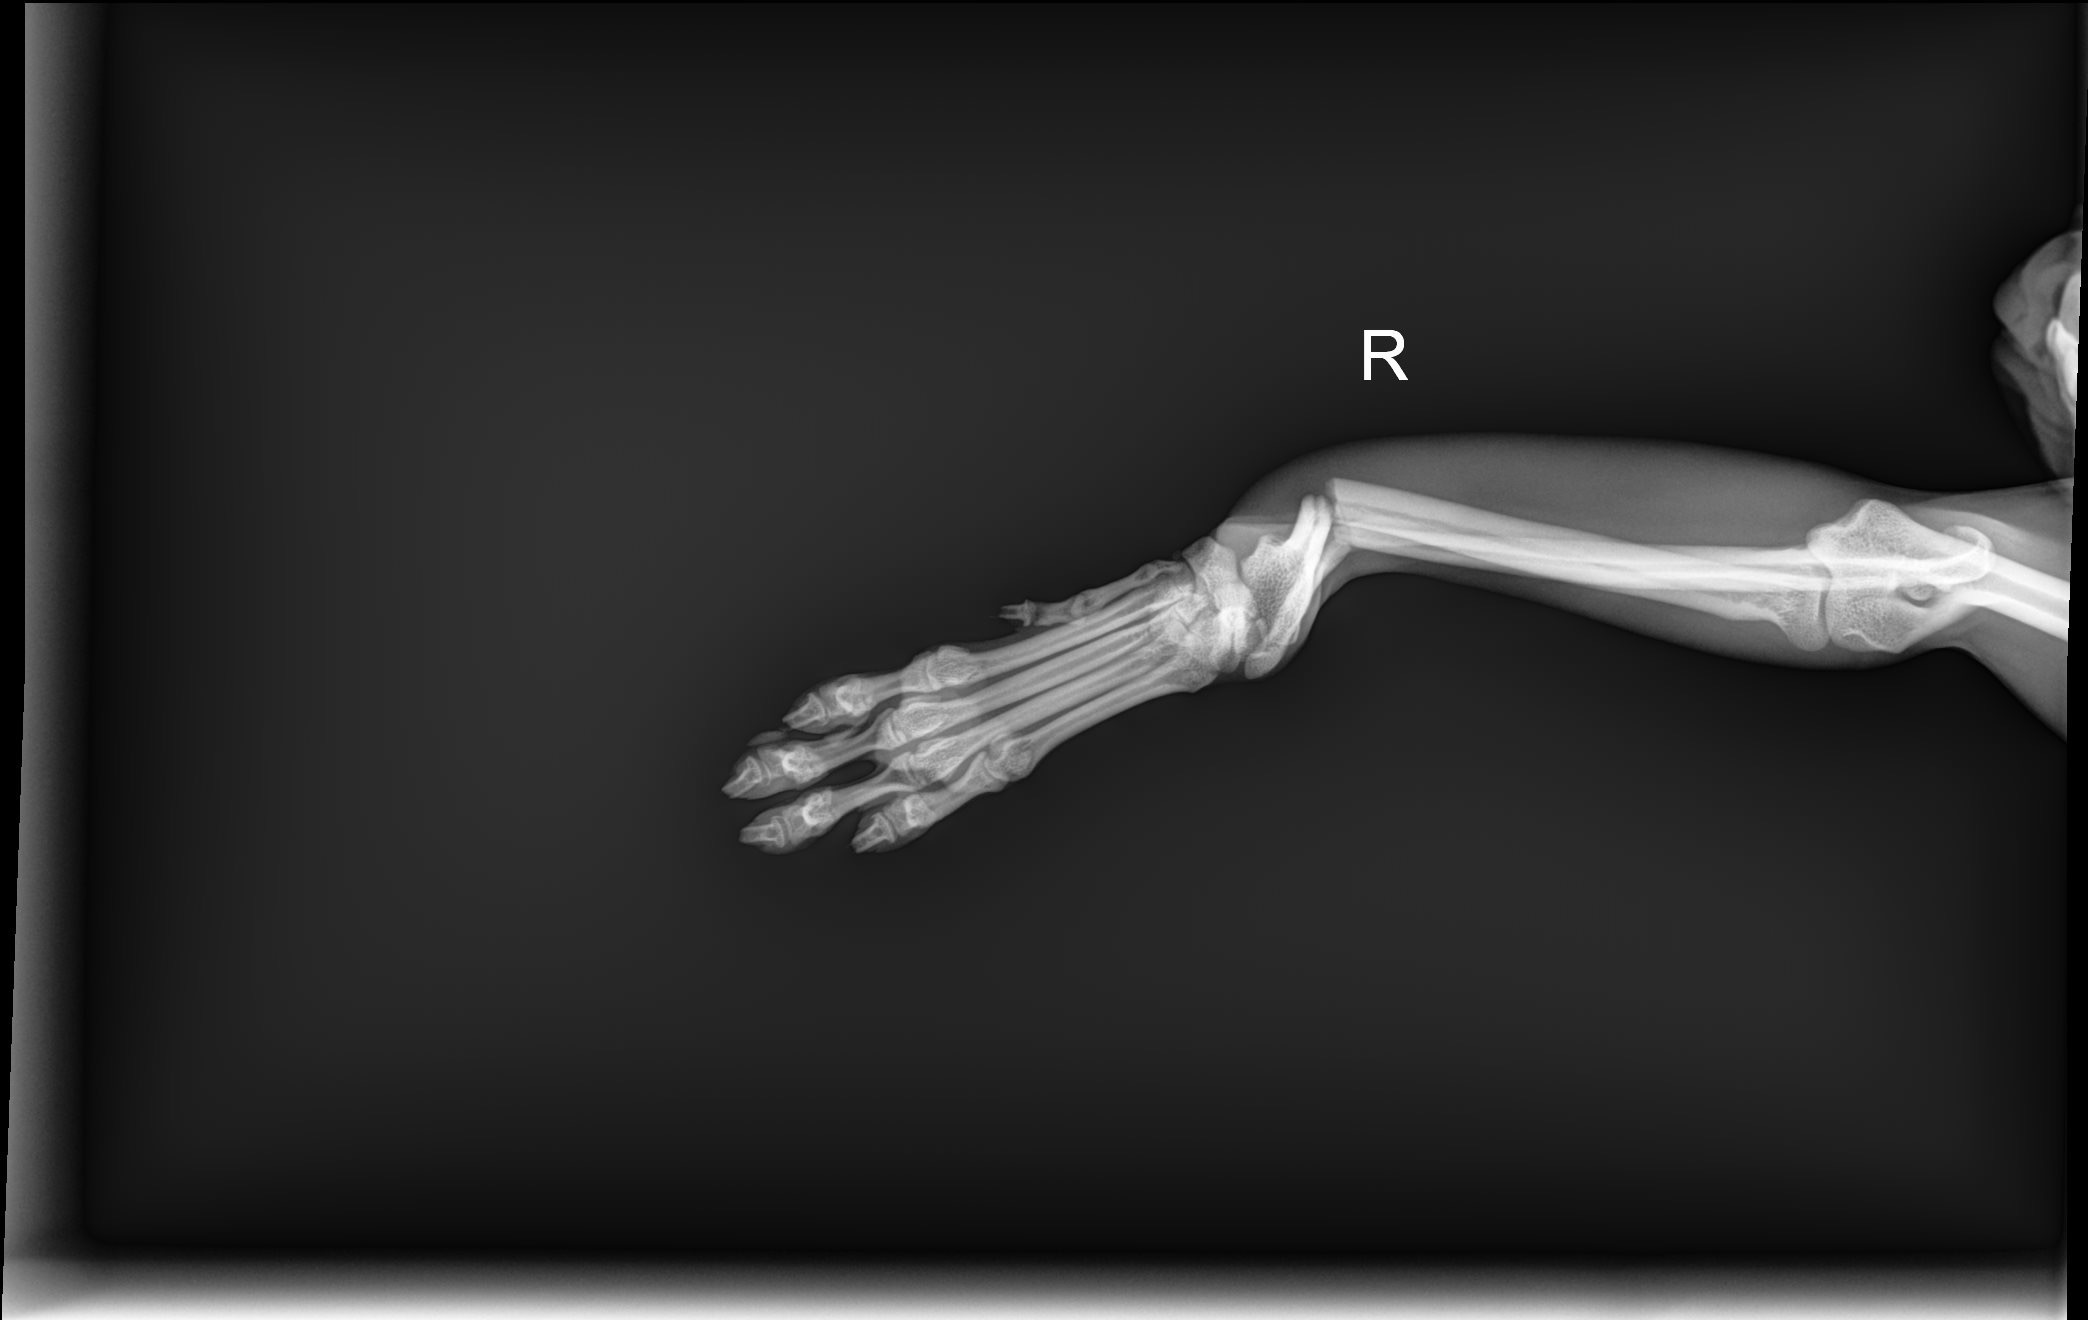

Hi everyone - meet Sushi. He is our 1-year-old, tripod Chihuahua. On December 30th, he slipped and took a tumble while hopping down from the couch and landed terribly wrong on his one front leg. Unfortunately, he broke both his radius and ulna, resulting in needing immediate surgery. He has been a very brave boy while getting it set and splinted in his cast.